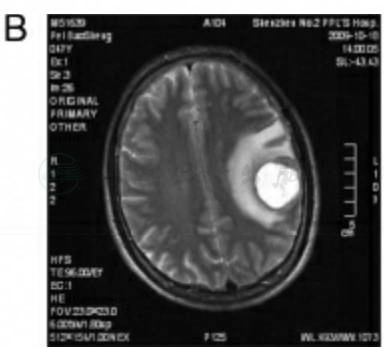

入院后行MRI见左颞叶占位,周围水肿明显,内有坏死组织,边缘可见环形强化,考虑恶性胶质瘤,转移癌待排(图5)。胸片、腹部B超未见异常。血常规结果正常。入院后急诊行左颞叶占位切除术,术中冰冻考虑“转移癌”,予切除肿瘤后去骨瓣减压。

图5 病例3MRI扫描